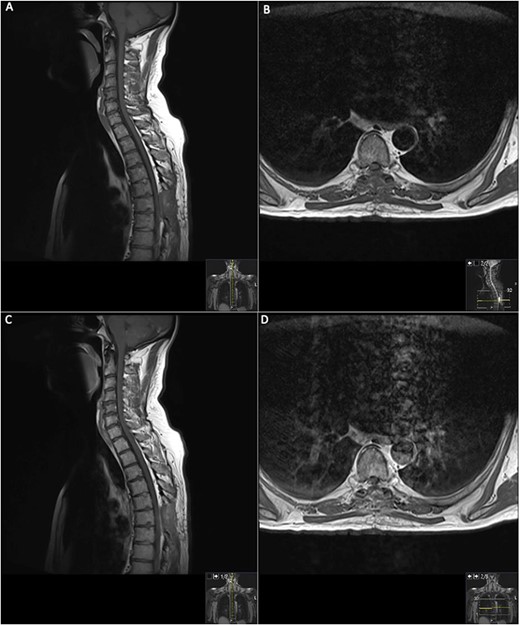

On presentation to A&E, his lower limb power was MRC 4/5 in the right leg and 5/5 in the left leg. Muscle power, sensation and reflexes in the upper limb were intact. He had upgoing plantars and normal lower limb reflexes, except for hyporeflexia in the right ankle reflex. Pinprick sensation was intact until T6 level, however, perianal light touch and pinprick sensation were absent. Urinary function and anal tone remained intact. An magnetic resonance imaging (MRI) spine was requested and discussed by the multidisciplinary team (MDT) (Fig. 1).

MRI on initial presentation; T1 (A) sagittal view sowing mild high signal changes alongside a T2 sequence transverse view (B) which shows the intermediate signal change; when compared with post-contrast T1 sagittal and transverse imaging (C) and (D), showing there is no significant enhancement post-contrast. MRI revealed an intramedullary spinal cord lesion at the level of T6 measuring 24 mm in craniocaudal dimension.